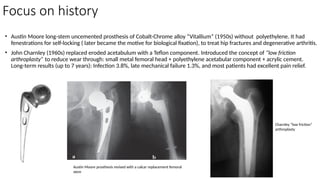

• Austin Moore long-stem uncemented prosthesis of Cobalt-Chrome alloy “Vitallium” (1950s) without polyethylene. It had

fenestrations for self-locking ( later became the motive for biological fixation), to treat hip fractures and degenerative arthritis.

• John Charnley (1960s) replaced eroded acetabulum with a Teflon component. Introduced the concept of “low friction

arthroplasty” to reduce wear through: small metal femoral head + polyethylene acetabular component + acrylic cement.

Long-term results (up to 7 years): Infection 3.8%, late mechanical failure 1.3%, and most patients had excellent pain relief.

Austin Moore prosthesis revised with a calcar replacement femoral

stem

Charnley “low friction”

arthroplasty